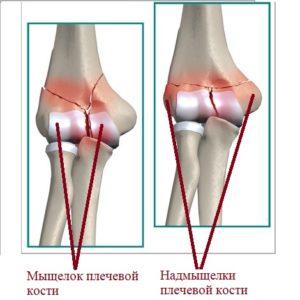

Согласно анатомическим особенностям, в дистальном сегменте плечевой кости выделяют один мыщелок и два надмыщелка (см. рис. 2).

Структура, находящаяся ближе к центру тела, называется медиальной, в то время как латеральной считается та, которая расположена дальше от центра (см. рис. 3).